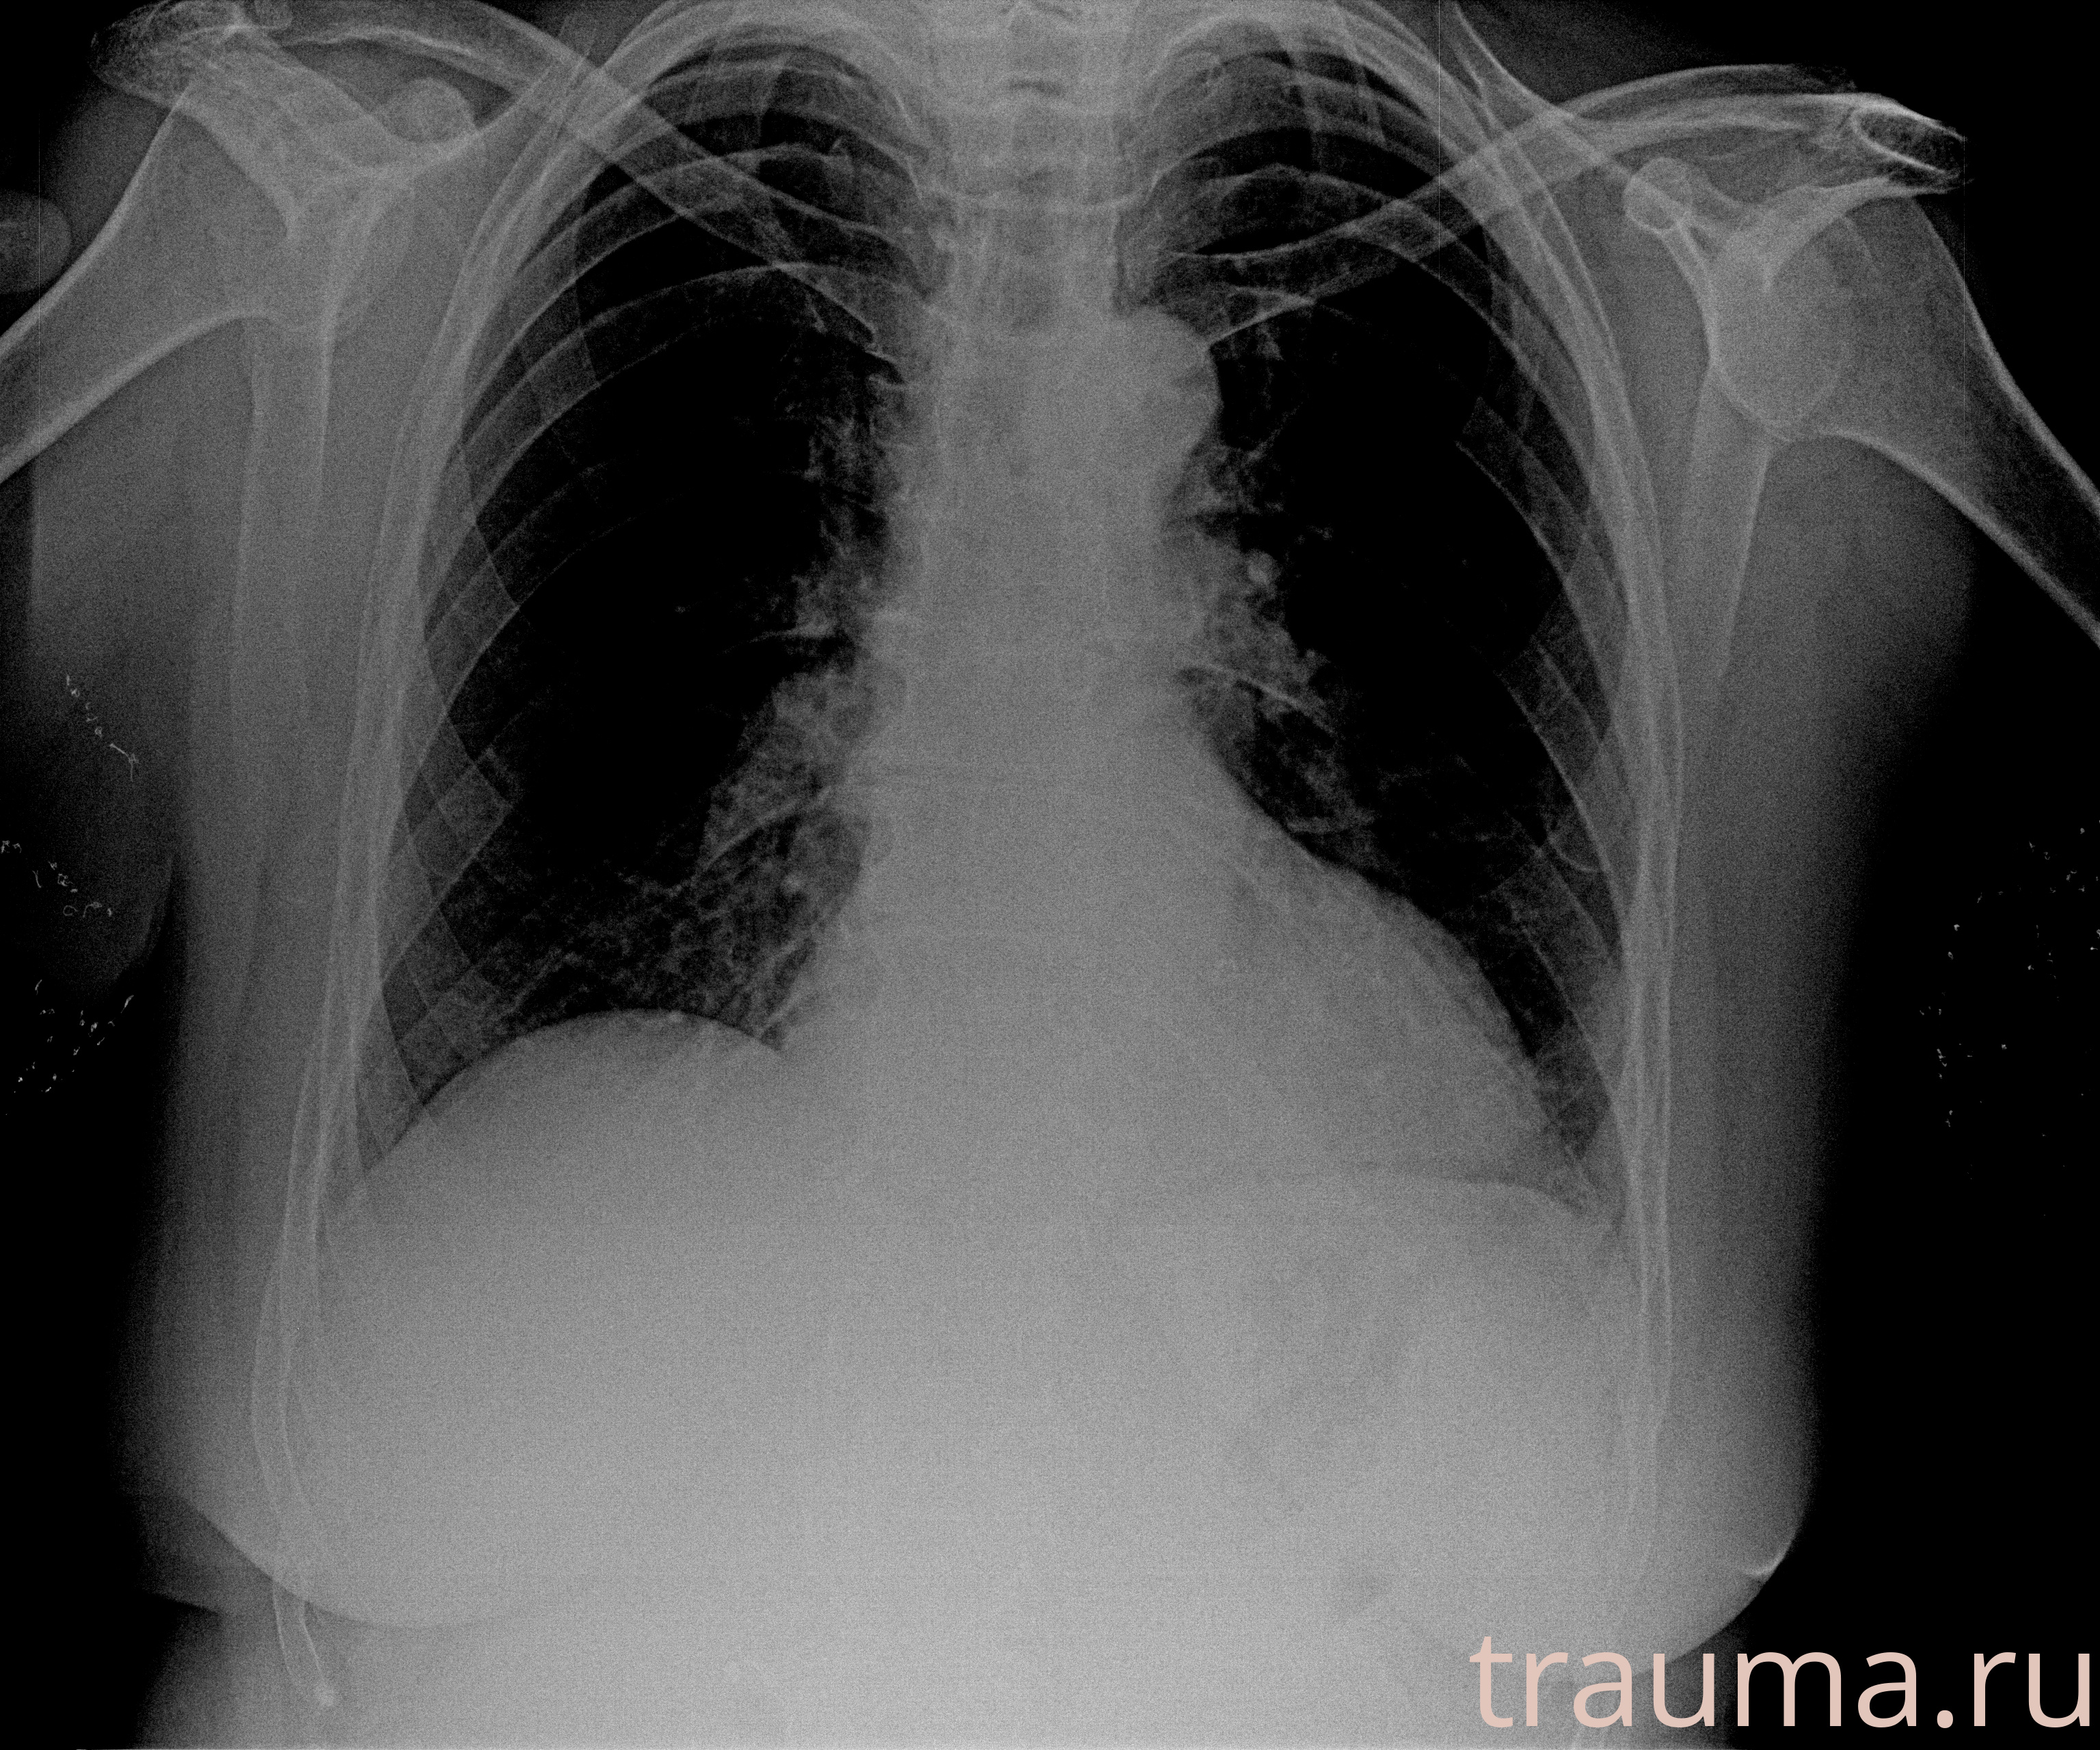

при переломе шейки бедра и пневмонии от компании МосРентген Центр - партнера Института имени Склифосовского

Рентген на дому: по вашему адресу приезжает врач-рентгенолог, травматолог-ортопед с мобильным рентгеновским аппаратом, проводит диагностику травмы или заболевания, делает необходимые рентгенограммы, дает рекомендации по дальнейшему лечению. Получить качественные снимки в домашних условиях возможно благодаря уникальной методике, разработанной МосРентген Центром для института  Склифосовского